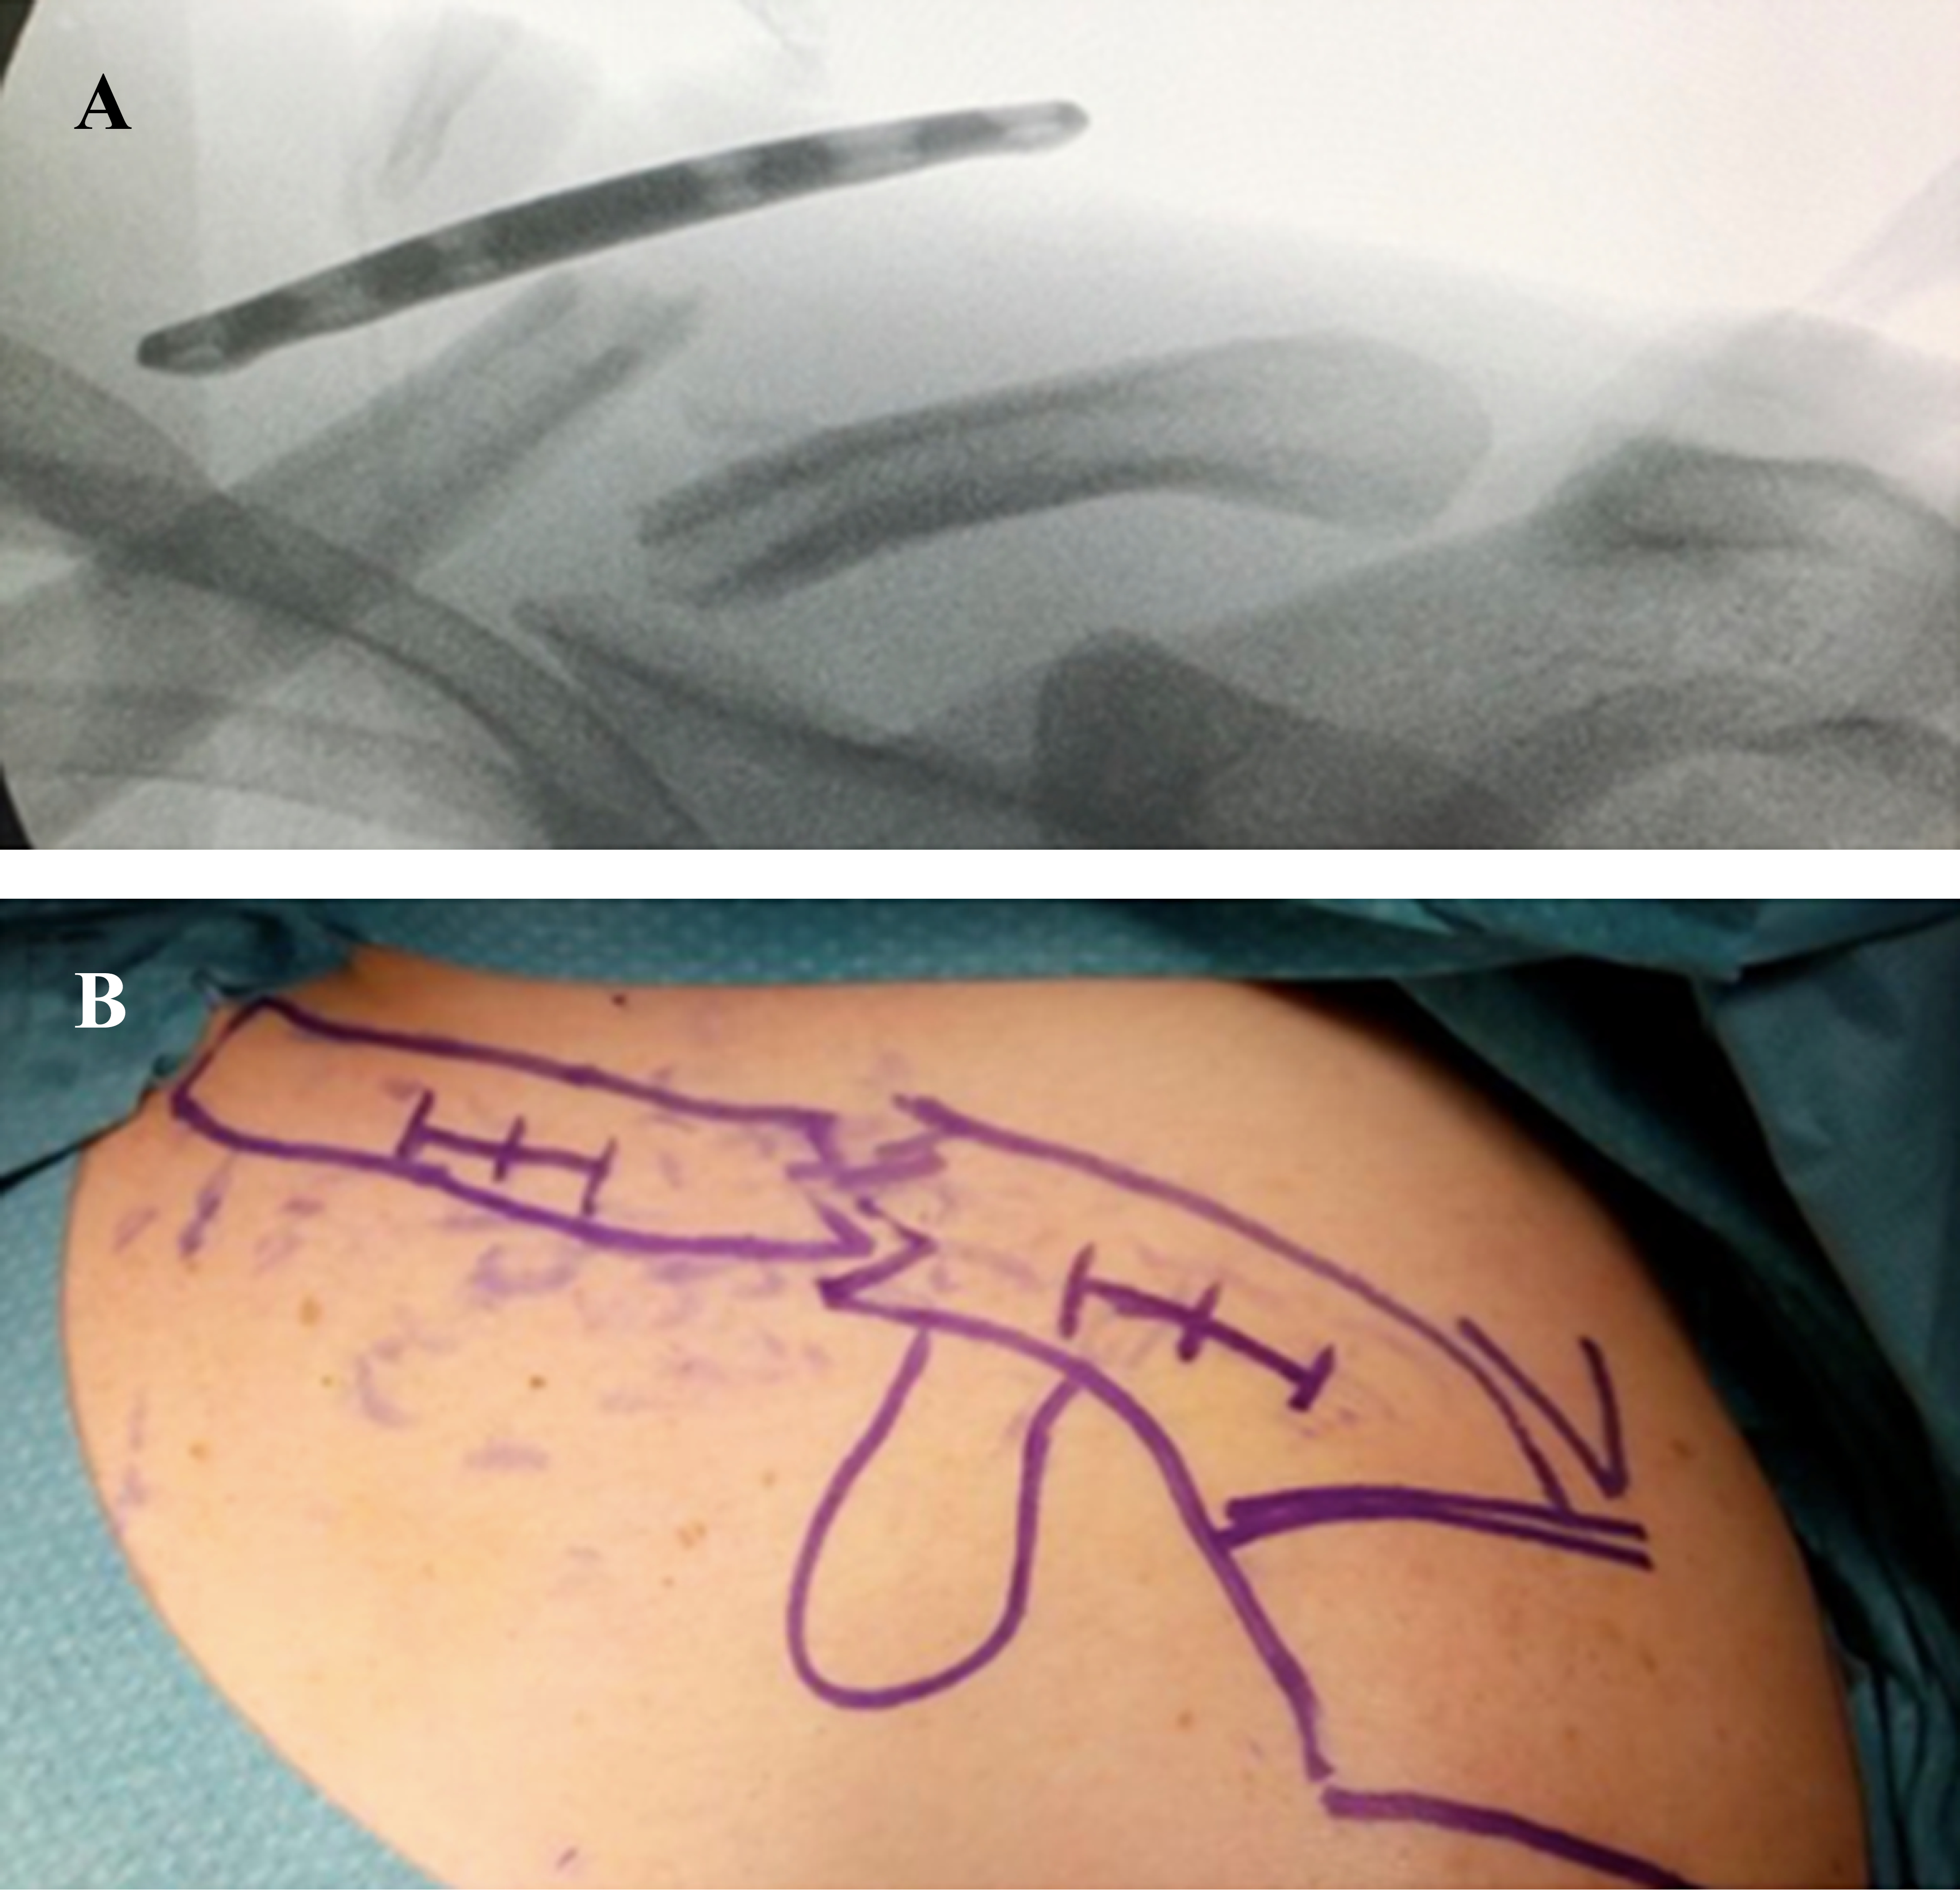

Posicionamiento y preparación del paciente: con el paciente en posición silla de playa bajo anestesia general más un bloqueo interescalénico, previa asepsia y antisepsia de la piel, se instalan campos quirúrgicos estériles dejando libre toda la extremidad superior a intervenir desde la zona esternal y base del cuello. Se posiciona el fluoroscopio con protección estéril posterior al paciente, de tal manera que permita obtener dos proyecciones claviculares en planos ortogonales entre sí, con una proyección anteroposterior para el control medio-lateral y un céfalo-caudal para el control anteroposterior tanto de la fractura como de la placa (Figura 1). Es importante que el hombro quede ubicado en la mesa quirúrgica sin que existan interferencias metálicas para poder obtener las distintas proyecciones fluoroscópicas durante la cirugía.

Técnica quirúrgica: con un lápiz marcador se delimitan las referencias óseas desde la articulación esternoclavicular como límite medial hasta la articulación acromioclavicular como límite lateral. Con ayuda del fluoroscopio y antes de realizar cualquier incisión cutánea, se selecciona la placa anatómica bloqueada más apropiada para la fractura, buscando un adecuado balance entre los orificios para tornillos proximales y distales al foco de fractura (Figura 2A). Una vez seleccionada la placa, ésta se posiciona sobre la piel y se demarcan dos abordajes cutáneos de máximo 20 mm a cada lado del foco de fractura (Figura 2B).